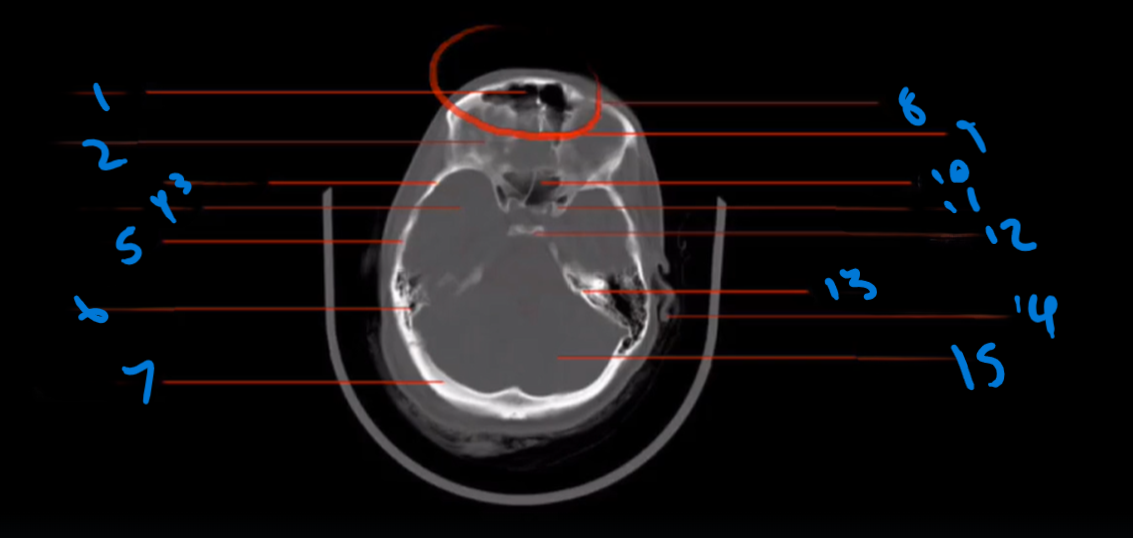

Landmark # 1

Frontal Sinus

Landmark 2

Orbital Roof

Landmark 3?

Greater Wing Sphenoid Bone

Landmark 4

Middle Cranial Fossa

Landmark 5

Temporal Bone

Landmark 6

Mastoid Air Cells

Landmark 7

Occipital Bone

Landmark 8

Superior Orbital Rim

Landmark 9

Crista Galli

Landmark 10

Sphenoid Sinus

Landmark 11

Anterior Clinoid Process

Landmark 12

Dorsum Sellae

Landmark 13

Petrous Ridge Temporal Bone

Landmark 14

Auricle

Landmark 15

Posterior Cranial Fossa